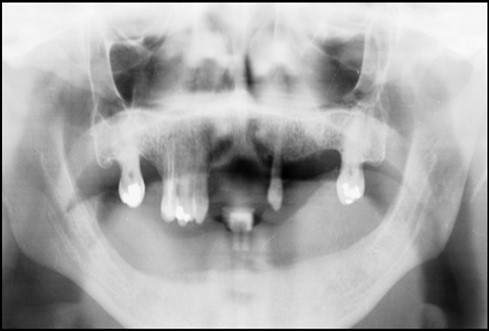

Post operatively after 3 months, osseointegration was evaluated clinically and radiographically (Figure 5a,b) and the implants were well prepared to receive the prosthesis. The second stage surgery was performed in which cover screws were removed and healing abutment were inserted into the implants (Figure 6). After a time period of two weeks, peri-implant soft tissue healing was examined, and existing denture was relined after relieving at the abutment site. Later, the healing abutment is removed using a 1.25 mm hex driver. Internal portion of the implant is irrigated and dried to make sure if it is free of debris and soft tissue. A periodontal probe was used to measure the gingival cuff height at the right and left canine site of implant location. Selected ball abutment were placed onto each implant using 1.25 mm hex driver and 30 Ncm torque wrench (Figure 7A).

Figure 5.a,b. Post-insertion radiographics in the mandibular area right,left,

a,b. Post-insertion radiographics  in the mandibular area right,left,

Figure 6.Panoramic radiograph after the insertion of two implants

Panoramic radiograph after the insertion of two                 implants